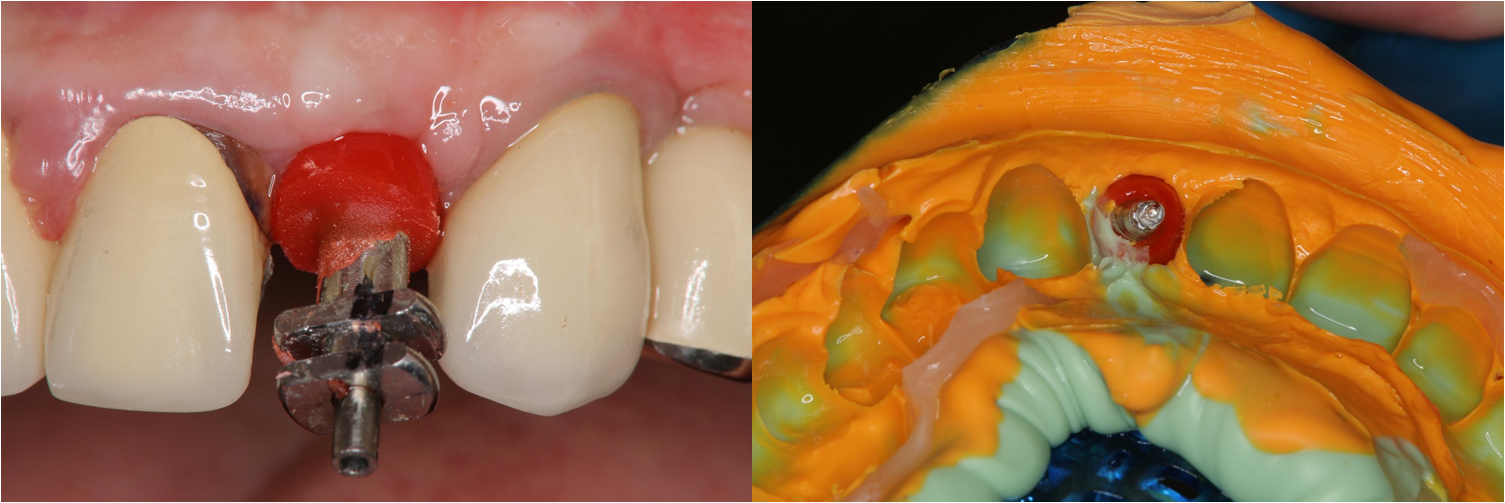

植體穩定後,癒合帽植入

印模上咬合器

塑形後再印模